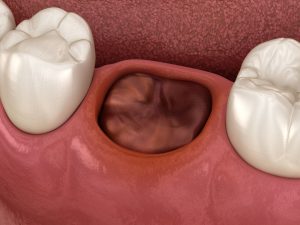

通常、抜歯後には、抜歯した穴(抜歯窩)に血液が溜まり、血の塊(血餅:けっぺい)というゼリー状のかさぶたが形成されます。

この血餅が、傷口を細菌や外気から守り、骨や歯ぐきが再生するための足場となります。

ですが、何らかの原因により血餅が正常に形成されない、あるいは剥がれて脱落してしまうことで、抜歯窩の底にある顎の骨がむき出しになり、外気や唾液、細菌に触れて炎症を起こします。この状態を「ドライソケット」と呼びます。

ドライソケットは、抜歯直後ではなく、抜歯後3日目から5日目頃に、痛みが急激に悪化することで発症に気づくケースがほとんどです。